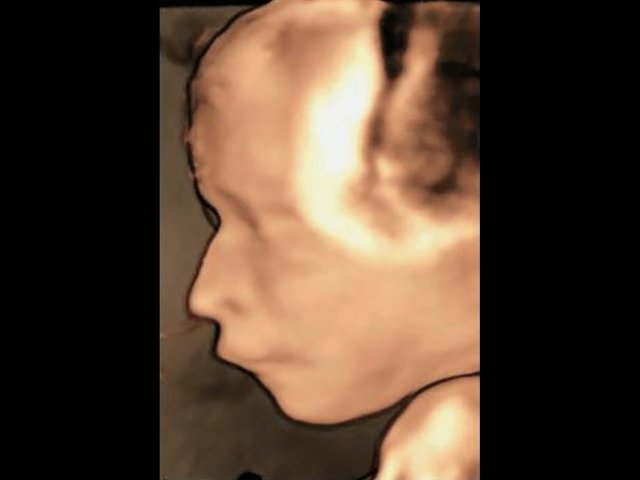

Революцией в пренатальной ультразвуковой диагностике явилось появление объемной эхографии, которая, обладая такими качествами, как неинвазивность, безопасность и возможность многократного применения у одной пациентки, имеет высокую информативность в исследовании анатомии плода и изучении его фенотипа. При применении различных режимов объемной эхографии абсолютно очевидно их преимущество по сравнению с обычным сканированием. Детально можно изучить лицо плода (рис. 1–4) в различные сроки беременности, начиная со сроков первого пренатального скрининга в 11–14 нед, конечности плода, причем не только их наличие и положение (рис. 5, 6), но и состояние и количество пальцев (рис. 7–9) как на руках, так и на ногах. Также можно изучить позвонки плода (рис. 10), состояние твердого нёба (рис. 11, 12), строение наружного уха (ушной раковины) (рис. 13), состояние основных швов черепа и родничков, исключая их преждевременное закрытие при кранисиностозах (рис. 14, 15).

Рис. 2. Нормальный профиль плода, 21 нед беременности.

Рис. 3. Нормальный профиль плода, 23 нед беременности.